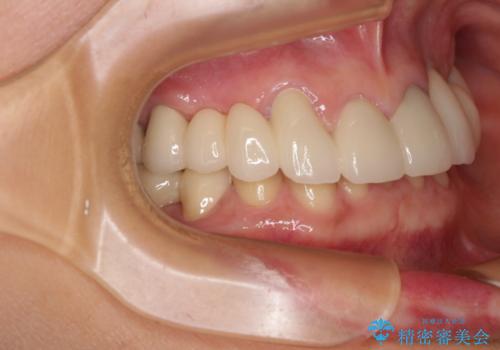

- 割れていると言われて放置してしまった歯や、前歯のデコボコなどが気になるとのことで来院された患者様です。

左上の歯は割れてしまっており、抜歯のうえインプラント治療が必要であり、他にも抜歯の必要な歯がある状態でした。

上顎はほぼ全ての歯をセラミッククラウンにて補綴治療を行う必要があるため、気になるデコボコや深い咬み合わせを改善するために下顎と上顎の臼歯部の矯正治療を行うこととしました。

過蓋咬合(下顎前歯が隠れてしまうほどの深い咬み合わせ)のため、スムーズに歯が動かず矯正治療に時間がかかりましたが、無事に仕上げることができました。